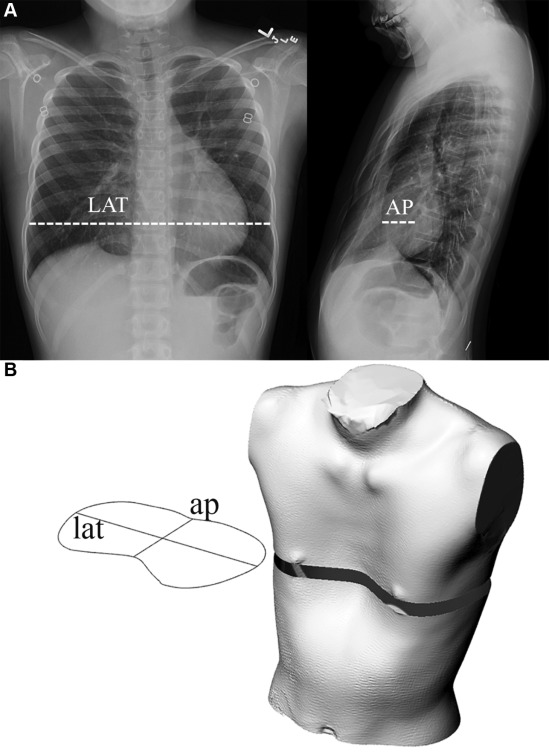

En sık rastlanan göÄŸüs duvarı sendromudur. Halk arasında kunduracı göÄŸsü olarak bilinir. Kaburga kemiklerinin ve sternumun (iman tahtası) içeriye (arkaya) çökmesi durumudur. Pektus ekskavatum sıklıkla doÄŸumsal pataloji olarak görüldüÄŸü gibi ilk bir yaÅŸ civarında ortaya çıkar. Erkeklerde daha sıklıkla görülür. OluÅŸum nedeni tam olarak bilinmemekle birlikte Mafran senderomu ve buna benzer sendromlarla bir arada görülebilir. Hastaların çoÄŸunluÄŸu göÄŸüs kafesi ÅŸekil bozukluÄŸu ÅŸikayeti ile doktora baÅŸvururlar. Spor yaparken erken yorulma, dayanıksızlık; sık yansıtılan ÅŸikâyetler arasındadır. Orta ve ileri düzey ÅŸikâyetlerde kalp iyice sola yerleÅŸir. ÇoÄŸu ileri düzey vakada kalp rahatsızlığını tetikler. Erken dönem ve düÅŸük açılara sahip vakalarda konservatif tedavi önemli geri dönüÅŸüm saÄŸlar. Vakum ve korse uygulaması göÄŸüs kafesinin normal pozisyonuna dönmesini saÄŸlar. Doktorun tavsiyesine göre uygulanan ortezler rutin süreçlerde kontrol edilmelidir. Uygulama yaşına ve deformasyona göre kullanım süresinde deÄŸiÅŸiklik gösteren korse uygulaması kemikleÅŸme yaşının dolmasına kadar oldukça olumlu çözüm sunmaktadır.

GöÄŸüs kafesinin ve sternumun (iman tahtası) öne doÄŸru çıkıntı yapmasıdır. Sternumun göÄŸüs kafesindeki kaburgalara göre aynı hizada olması gerekirken orta kısmının öne doÄŸru çıkarak konkav görüntü oluÅŸturmasıdır. KuÅŸlarda görülen göÄŸüs kafesi ÅŸekline benzediÄŸi için güvercin göÄŸsü benzemesi yapılır. ÇoÄŸu çocukta göÄŸüs kafesi simetrik olarak çıkıntı yaparken bazı vakalarda asitmetri görülebilir. Erkeklerde daha sık görülür. ÇeÅŸitli hastalıklar tetikleyici olabilir: